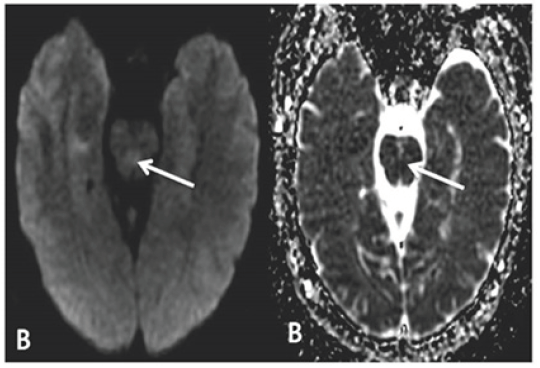

The patient is a 66-year-old male with hypertension, hypercholesterolemia and depression who presented after sudden onset of severe headache, vertigo, diplopia, diaphoresis, photophobia and blurred vision. Headache was described as a sharp pain radiating from the back of the head; severe vertigo led to persistent nausea with emesis. Symptoms were exacerbated by change in position and improved in supine positioning with eyes closed. He denied jaw claudication, scalp tenderness or myalgias. Neurologic exam was remarkable for horizontal nystagmus in both right and left gaze, up-beat nystagmus in up-gaze and mild gait ataxia. Motor and sensory exam was normal. Labs were unremarkable outside of leukocytosis to 18. Non-contrast CT scan of the head was unremarkable. MRI brain revealed diffusion-weighted changes in the mid-pons (Figure 1B). Pontine stroke was initially thought to be secondary to small vessel disease. Pharmacological management of vertigo with diphenhydramine, lorazepam, ondansetron and meclizine were attempted, yet unsuccessful. Transthoracic echocardiogram demonstrated mild left ventricular hypertrophy, but no other significant abnormalities and cardiac telemetry monitoring was negative for arrhythmia.

Figure 1B:MRI imaging of patient 2, showing DWI and corresponding ADC abnormality in the mid pons, representing acute infarct.